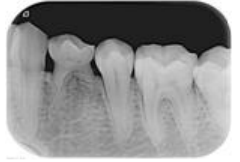

65.下圖根尖X光片中,白色箭頭所指為何構造?

(A)Periodontal ligament space (B)Alveolar crest (C)Cementum (D)Lamina dura